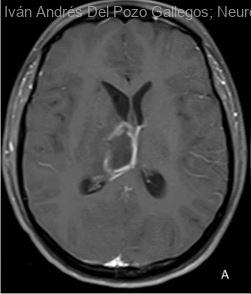

Mujer | 25 años

Diagnóstico final: ABCESO CEREBRAL

Paciente de 25 años, sin antecedentes clínicos de importancia, que acude al servicio de urgencia con historia de 1 semana de intensa cefalea frontal pulsátil, vómitos sin nausea, dolor abdominal y fiebre diaria. Al examen...